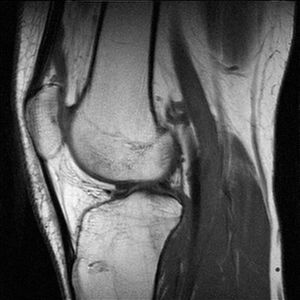

تصوير رنين مغناطيسيبالإنگليزية: Magnetic resonance imaging (MRI) هي وسيلة تصوير طبي لتوضيح التغييرات الباثولوجية في الأنسجة الحية و للرنين المغناطيسي أستخدمات غير طبية ومن الناحية الفيزيائية فهي تعتمد على ما يسمى بالطنين المغناطيسي النووي RMN . يعتبر التصوير بالرنين المغناطيسي من الفحوص المكلفة وغير متوفرة بشكل دائم في كثير من المستشفيات, وهناك صعوبات عند عمل هذا النوع من الأشعة عند المرضى الذين يخافون من الأماكن المغلقة أو المرضى الذين يشتكون من سمنة مفرطة.

للرنين المغناطيسي أستخدمات تشخيصية متعددة لأنه قادر و بدقة عالية على تصوير الأنسجة الداخلية دون التركيز على العظام مما يساعد على تشخيص الأورام خبيثة أو حميدة التي تنبع من الأنسجة

T2-weighted MRI